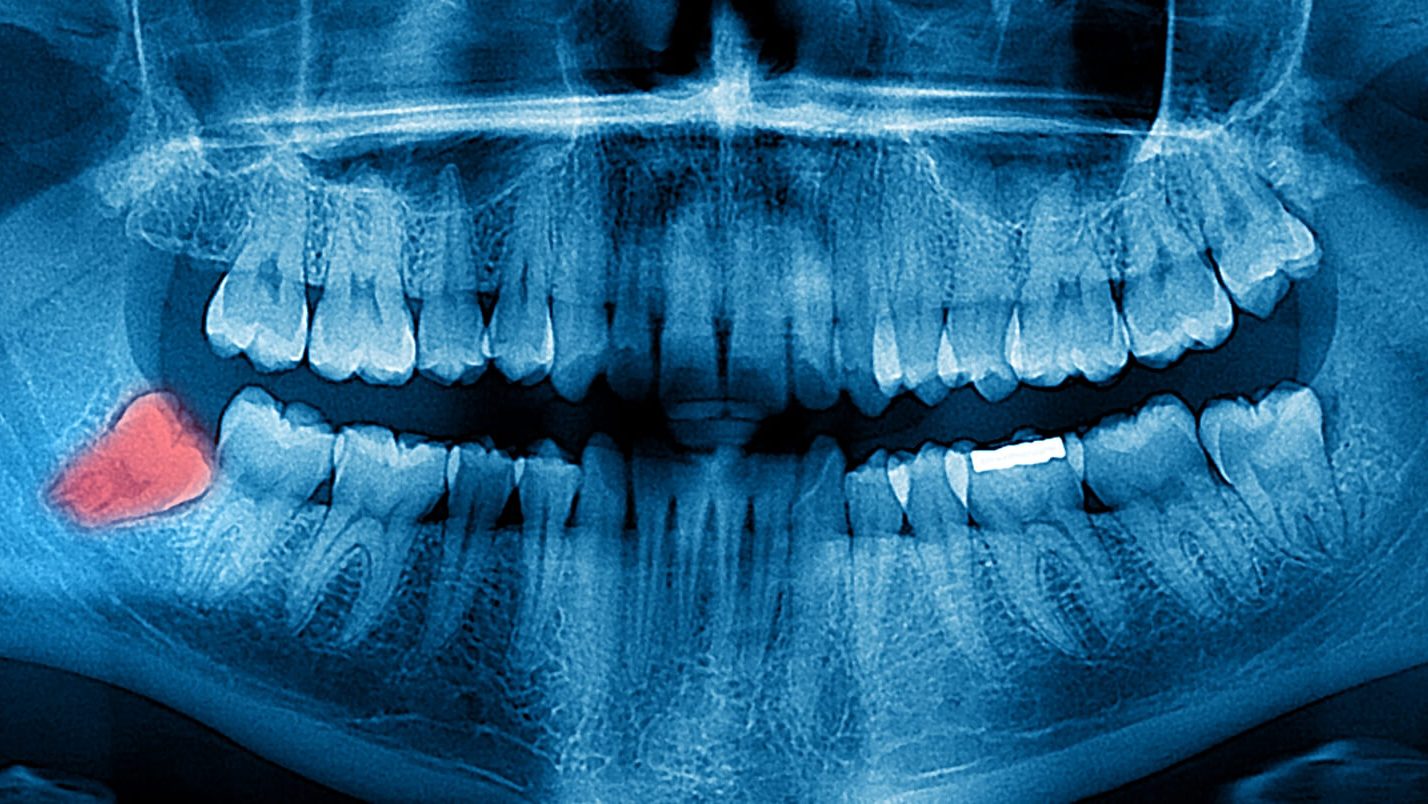

tooth Cysts: The wisdom tooth develops in a sac within the jawbone. The sac can fill with fluid, forming a cyst that can damage the jawbone, teeth and nerves. Rarely, a tumor — usually noncancerous (benign) — develops. This complication may require removal of tissue and bone.

tooth Decay: Partially impacted wisdom teeth appear to be at higher risk of tooth decay (caries) than other teeth. This probably occurs because wisdom teeth are harder to clean and because food and bacteria get easily trapped between the gum and a partially erupted tooth.

tooth Gum disease: The difficulty cleaning impacted, partially erupted wisdom teeth increases the risk of developing a painful, inflammatory gum condition called pericoronitis (per-ih-kor-o-NI-tis) in that area.